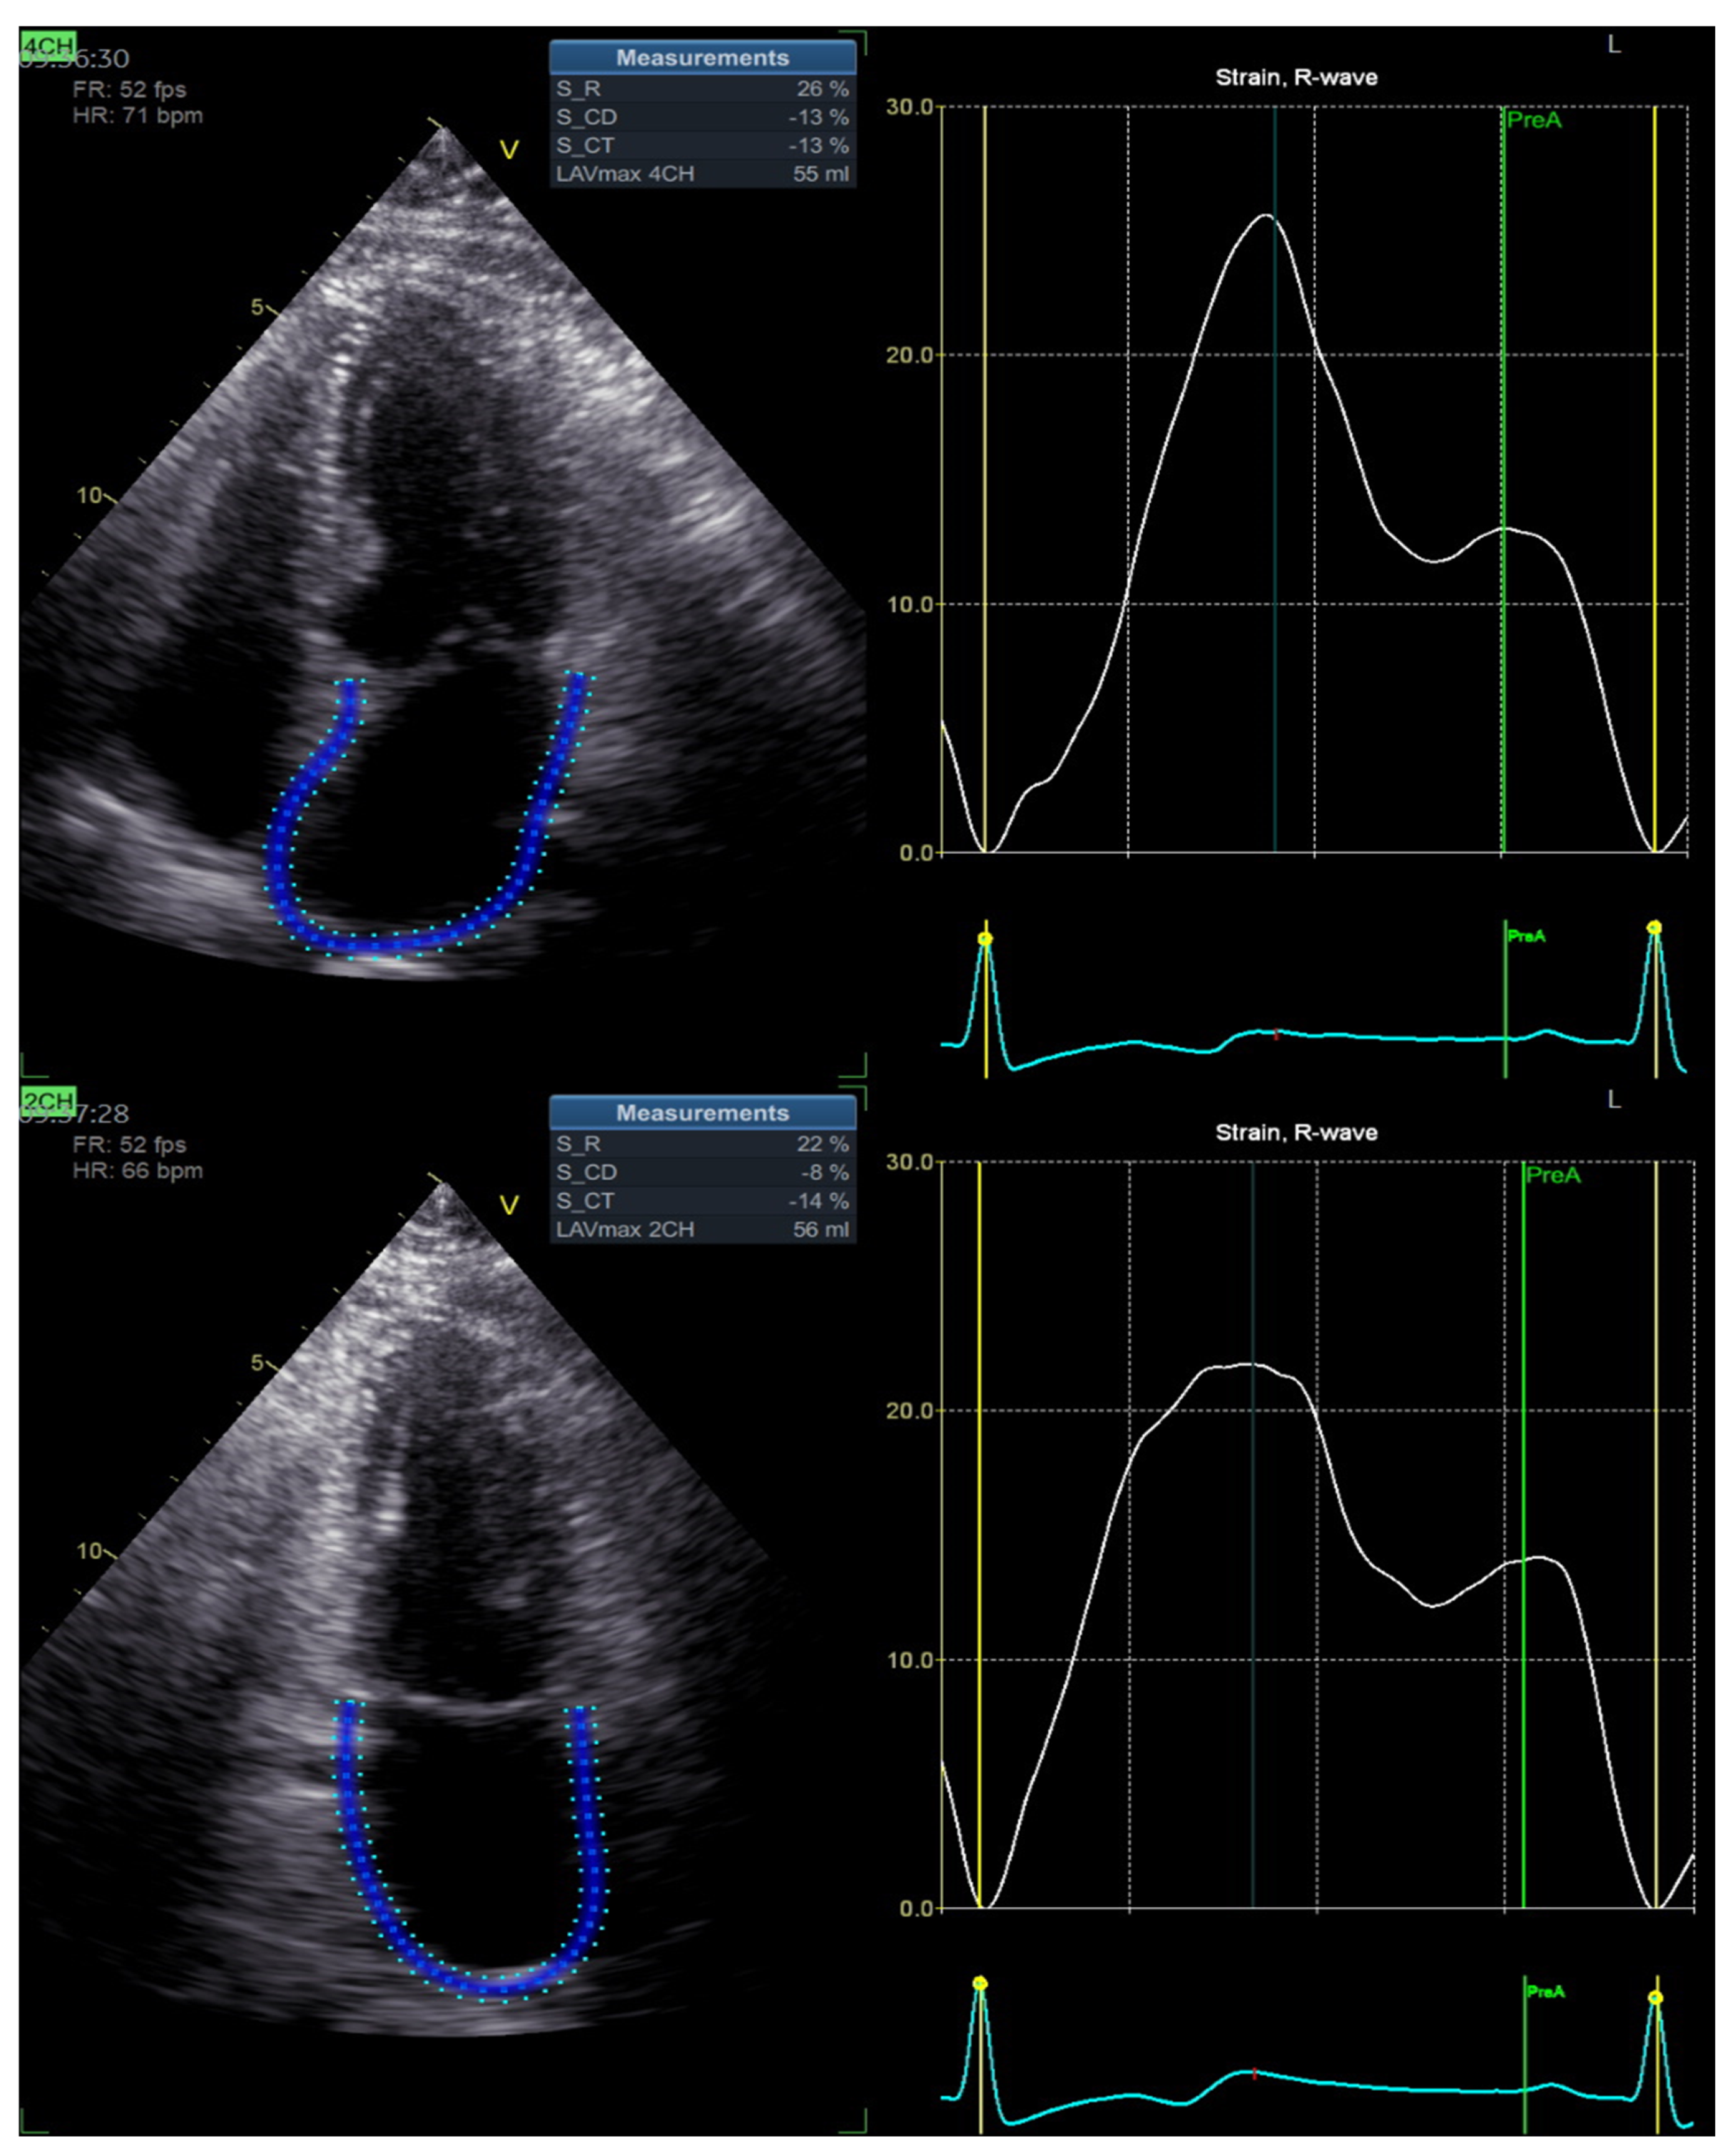

| PALS, % | 20 | 27 | 0.002 |

| PACS, % | 14 | 15 | 0.318 |

| LAVI, mL/m2 | 28.6 ± 5.1 | 27.2 ± 4.9 | 0.042 |

| LV GLS, % | −11.6 ± 4.7 | −19.3 ± 3.2 | 0.028 |